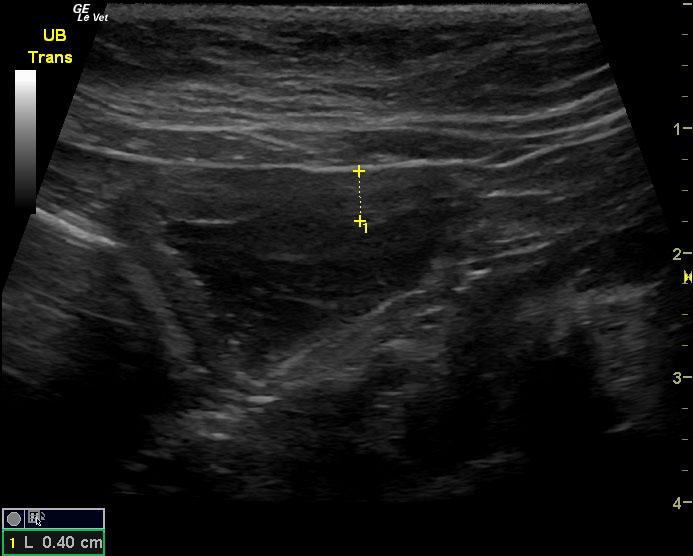

The urinary bladder in this patient revealed dependent debris that measured 2.1 cm in length. The bladder wall presented minor, apical ventral wall thickening. Suspended debris was also evident. The bladder wall thickening appeared to be concentric throughout with some loss of mural detail, and measured 0.4 cm at minor repletion. The pelvic urethra was also thickened. These images are most consistent with interstitial cystitis with minor potential for bladder lymphoma. The kidneys revealed largely normal size and structure; corticomedullary definition and ratio (cortex 1/3 of medulla) were essentially maintained with minor loss of curvilinear pattern. The cortices presented largely uniform texture with some echogenic changes that are not likely of clinical significance at this time.